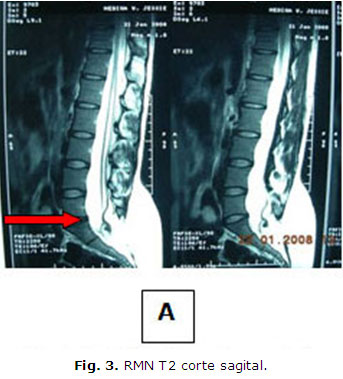

Paciente femenina de 22 años, con antecedentes de salud hasta hace dos años en que comienza a presentar dificultad para orinar, acude a la consulta de urología del Hospital "Mario Catarino Rivas". Se diagnostica una retención urinaria y se le coloca una sonda vesical de forma permanente, (Fig. 2). Es estudiada durante dos años sin encontrar una patología urológica que explique su enfermedad, por lo que se remite a consulta de Neurocirugía. Al examen físico se observa como dato positivo el aumento de volumen a nivel lumbosacro, redondeado de aproximadamente 10 cm. de diámetro, movible, no doloroso, poco adherido a planos profundos que impresionaba ser compatible con un lipoma lumbosacro. Se realiza el estudio de RMN lumbosacro, encontrándose la médula anclada en relación con la masa lumbosacra antes descrita (Fig. 3 y Fig. 4 ) (imagen sugestiva de lipomiemomeningocele). La paciente es preparada para la cirugía. Se efectúa una laminectomía lumbosacra con la resección de la masa tumoral y liberación de las adherencias del saco dural y raíces lumbosacras. Se retira la sonda vesical a las 48 horas de operada (Fig. 5) y recupera sus funciones vesicales a la normalidad. Ha sido seguida por consulta externa durante seis meses y se mantiene asintomática (Fig. 6 ). Se confirma por anatomía patológica el diagnóstico de lipoma lumbosacro.